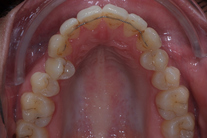

Ung kvinna som tidigare haft tandreglering. Upplever inte att tänderna står i en fin tandbåge. 11 månaders behandling med genomskinliga Invisalignskenor resulterade i ett fint leende.